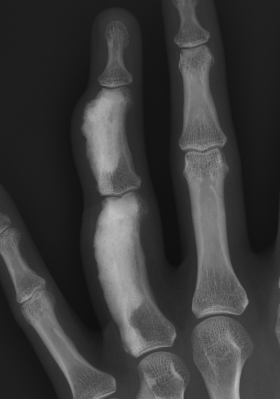

X-ray

Sclerotic lesions of bones

- undulating cortical hyperostosis

- look like wax dripping down the side of a candle

Periosteal bone formation with dense cortical bone

Marked endosteal sclerosis with marrow fibrosis